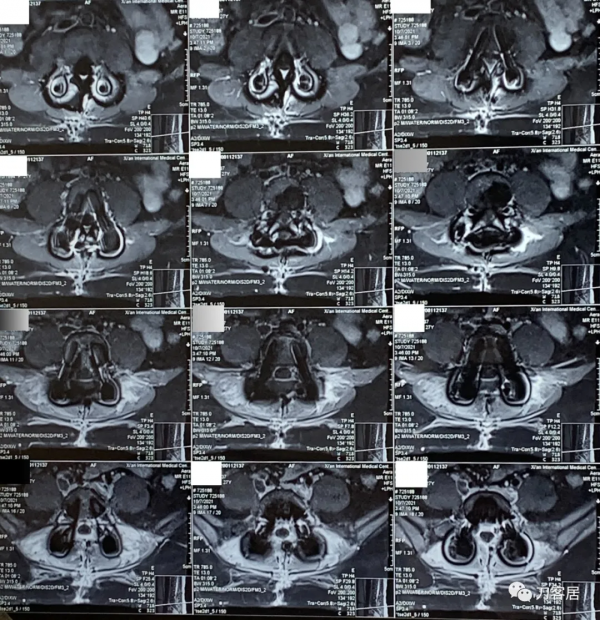

圖20. 20211007術後44天,腰椎MRI提示腰椎切口內液性聚集,但切口周圍軟組織內混雜訊號好轉。

圖21. 20211007術後44天,腰椎MRI提示腰椎切口內液性聚集,但切口周圍軟組織內混雜訊號好轉。

圖22. 20211007術後44天,腰椎MRI提示腰椎切口內液性聚集,但切口周圍軟組織內混雜訊號好轉,但該T1相提示術野後部軟組織內仍有異常訊號影。

圖23. 20211007術後44天,腰椎MRI提示腰椎切口內液性聚集,但切口周圍軟組織內混雜訊號好轉,但該T1相提示術野後部軟組織內仍有異常訊號影。

圖24. 20211007術後44天,腰椎MRI提示腰椎切口內液性聚集,但切口周圍軟組織內混雜訊號好轉,但該T1相提示術野後部軟組織內仍有異常訊號影。

圖25. 20211007術後44天,腰椎MRI橫截面掃描提示腰椎切口內液性聚集,但切口周圍軟組織內混雜訊號好轉,但術野後部軟組織內仍有異常訊號影。

圖26. 20211007術後44天,腰椎MRI橫截面掃描提示腰椎切口內液性聚集,但切口周圍軟組織內混雜訊號好轉,但術野後部軟組織內仍有異常訊號影。

圖27. 20211007術後44天,腰椎MRI橫截面掃描提示腰椎切口內液性聚集,但切口周圍軟組織內混雜訊號好轉,但術野後部軟組織內仍有異常訊號影。